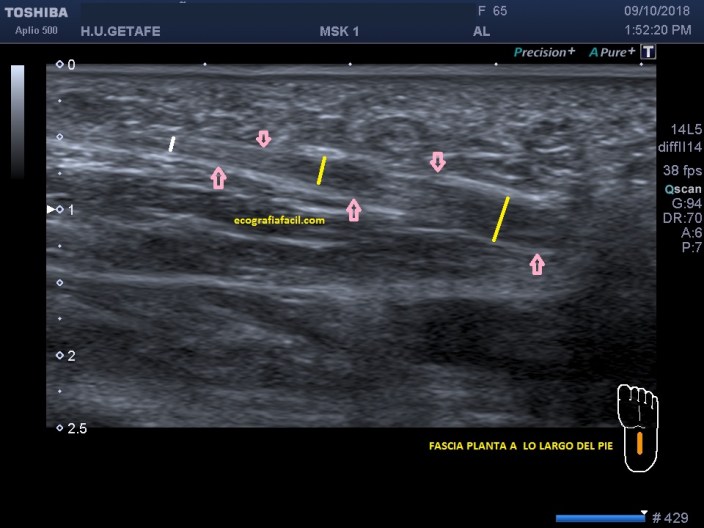

Una vez visualizada la zona crítica, que es la del apoyo del calcáneo, seguimos la fascia por el periplo de la planta del pie hasta la cabeza de los metatarsianos, es raro, pero ocasionalmente podemos encontrar inflamación en este trayecto, que como puede observar va perdiendo calibre a medida que va separándose del calcáneo, exista o no, patología…te lo marco con rayas y flechas para que sigas el discurrir de las fibras y las líneas para ver como pierde tamaño.

En la imagen ves como profundo y cerca del calcáneo la imagen es más hipoecogénica, es decir, patológica, recuperando la normalidad a medida que se aleja de esa zona afectada.

Observa la colocación del pictograma para ver cómo se coloca la sonda, la estructura es pequeña y anisotrópica, ojo con eso…

Once the critical zone has been studied, which is the calcaneal support, is visualized, we follow the fascia from the path of the sole to the metatarsal head, it is rare, but occasionally we can find inflammation in this path, which as you can see losing caliber as it separates from the calcaneus, whether or not there is pathology … I frame it with lines and arrows so you can follow the flow of fibers and lines to see how it loses size.

In the image you see how deep and close to the calcaneus the image is more hypoechoic, that is, pathological, recovering normality as it moves away from that affected area.

Observe the placement of the pictogram to see how the probe is placed, the structure is small and anisotropic, eye on it …